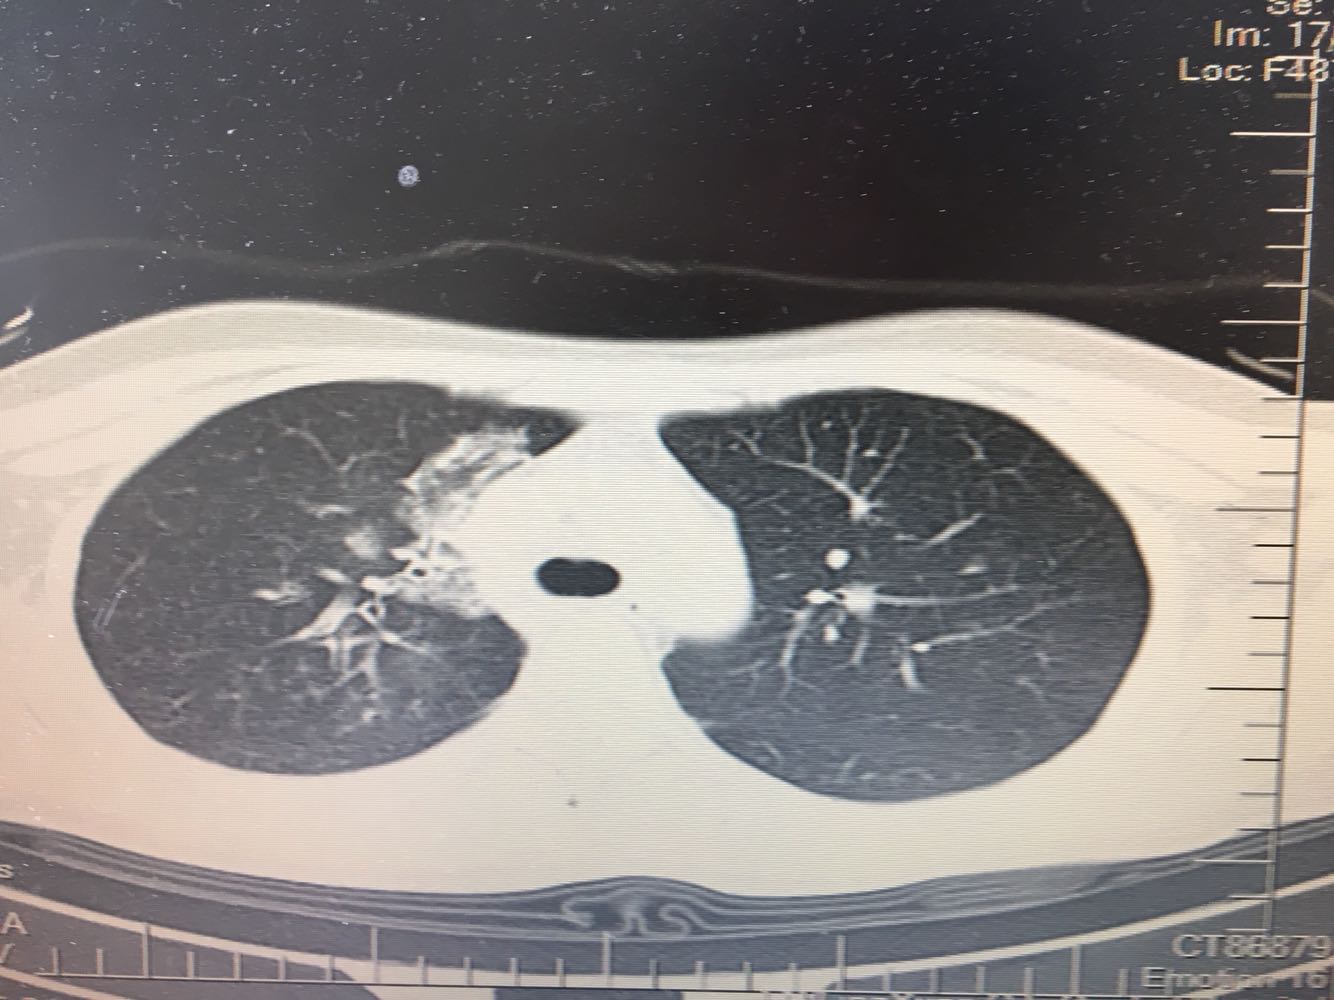

女,26岁,咳嗽1周,咳痰不畅,咽喉痒,口服阿莫西林无好转,昨日发热,体温38.5摄氏度,于门诊查肺CT后以肺炎收入院,病来无盗汗,无咳血,无消瘦及乏力,无头痛,无肢体酸痛,饮食睡眠可,二便正常

神清言明,咽部无充血,扁桃体不大,双肺呼吸音清,无罗音,服软无压痛。

支原体肺炎?肺结核?

支原体抗体1:160,结核抗体弱阳性。支原体肺炎个别可见上叶病变,该患无结核中毒症状,考虑支原体肺炎可能性大,但肺尖为结核好发部位,需要抗炎治疗后复查观察疗效。